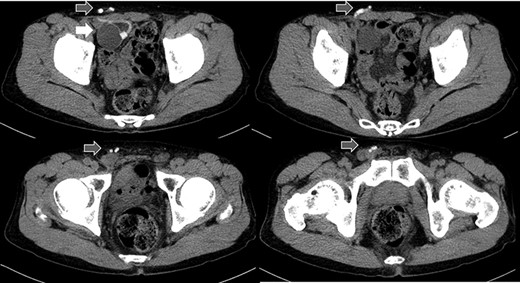

Abdominal CT in Case 1: CT showed that there was a balloon nearby the bladder and the tube went beside the rectus abdominis muscle from abdominal cavity; balloon, white arrow; tubes, gray arrows.

A 79-year-old male was referred to our institute for the treatment of right IH. He had received AUS implantation for the treatment of incontinence after RP for prostate cancer. Abdominal

computed tomography (CT) showed right IH and a balloon that was placed by the bladder and a connecting catheter that went through the lateral side of the rectus abdominis muscle (Fig. 2). In the operation, we performed ultrasonography (US) at first and it demonstrated that the catheter was running through the inguinal canal (Fig. 3). When we incised the aponeurosis of the external abdominal oblique muscle, the catheter of the AUS was observed in the inguinal canal (Fig. 4). We identified the hernia sac protruding from the inguinal ring and diagnosed it as an indirect IH. The adhesion was too hard to separate the catheter from the pubis and posterior wall of the inguinal canal around pubis. Then, the IH was repaired using the Lichtenstein technique; however, the mesh near the pubis could not be spread as ordinarily.

A 75-year-old male was referred for the treatment of a right IH. He also had received AUS implantation for a similar medical course. Abdominal CT demonstrated that a balloon was located beside the bladder and that the connecting catheter went through the rectus abdominis muscle and reached to the right scrotum through the subcutaneous layer (Fig. 5). The catheter was palpable subcutaneously; therefore, skin incision was placed on the outer site rather than in the normal situation. The diagnosis was indirect hernia and we did not observe any components of the AUS in the inguinal canal and repaired it using the Lichtenstein method.

Abdominal CT in Case 2: the balloon was located near the bladder and the tube went through rectus abdominis muscle; balloon, white arrow; tubes, gray arrows.